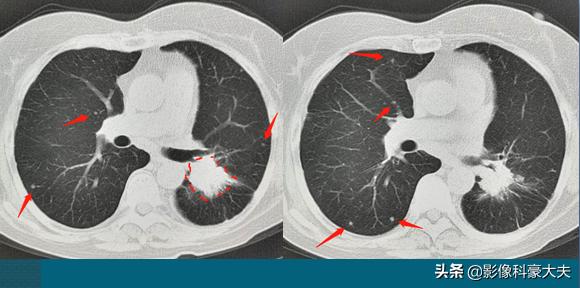

这位病人才61岁,咳嗽1个月,伴有喘息和憋气,肺部CT发现左侧中心型肺癌,3.6×2.6cm,不算大,却已经无法切除了,因为双肺见到十多个像黄豆大小的转移瘤,晚期了……

这位病人的生存期,相对比较乐观!如果基因检测阳性,通过靶向治疗为主的综合治疗,还有机会生存3年以上,甚至10年!